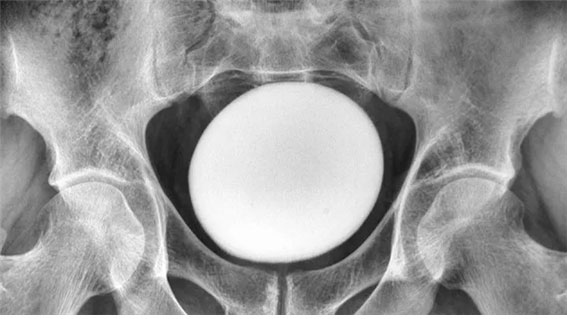

“배가 딱딱해” 35세 男, 방광서 거대한 ‘이것’ 발견… 뭐였을까?

비뇨기질환

| | 최소라 기자

2026/01/10 07:00